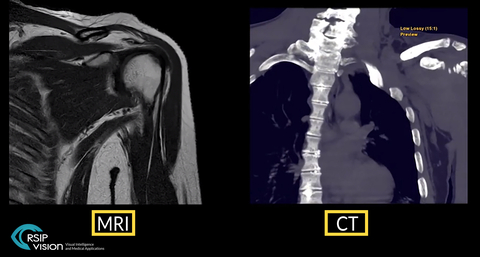

TEL AVIV, Israel & SAN JOSE, Calif.– RSIP Vision, an experienced leader in driving innovation for medical imaging through advanced AI and computer vision solutions, today announces a new tool for Total Shoulder Arthroplasty (TSA) planning. This tool performs segmentation of the shoulder bones from shoulder MRI scan, which is usually performed in shoulder healthcare. The segmentation output undergoes super-resolution enhancement to overcome inherent MRI resolution limitations. The end-result is a high-quality, 3D model of the shoulder bones, which allows exceptional planning for TSA, without the need for a CT scan for planning. This new vendor-neutral technology is available to third-party MRI manufacturers and viewer solutions, allowing an accurate and radiation-free method for TSA planning.

RSIP Vision’s new tool utilizes the shoulder MRI scan, without compromising on resolution quality. It automatically segments the humerus and scapula from the scan. The segmentation output goes through another neural network, trained to upgrade segmentation resolution, thus producing a super-resolution model despite the original scan limitations. This output is as-good as CT-based models, without the need for an additional scan, and can be used for procedural planning.